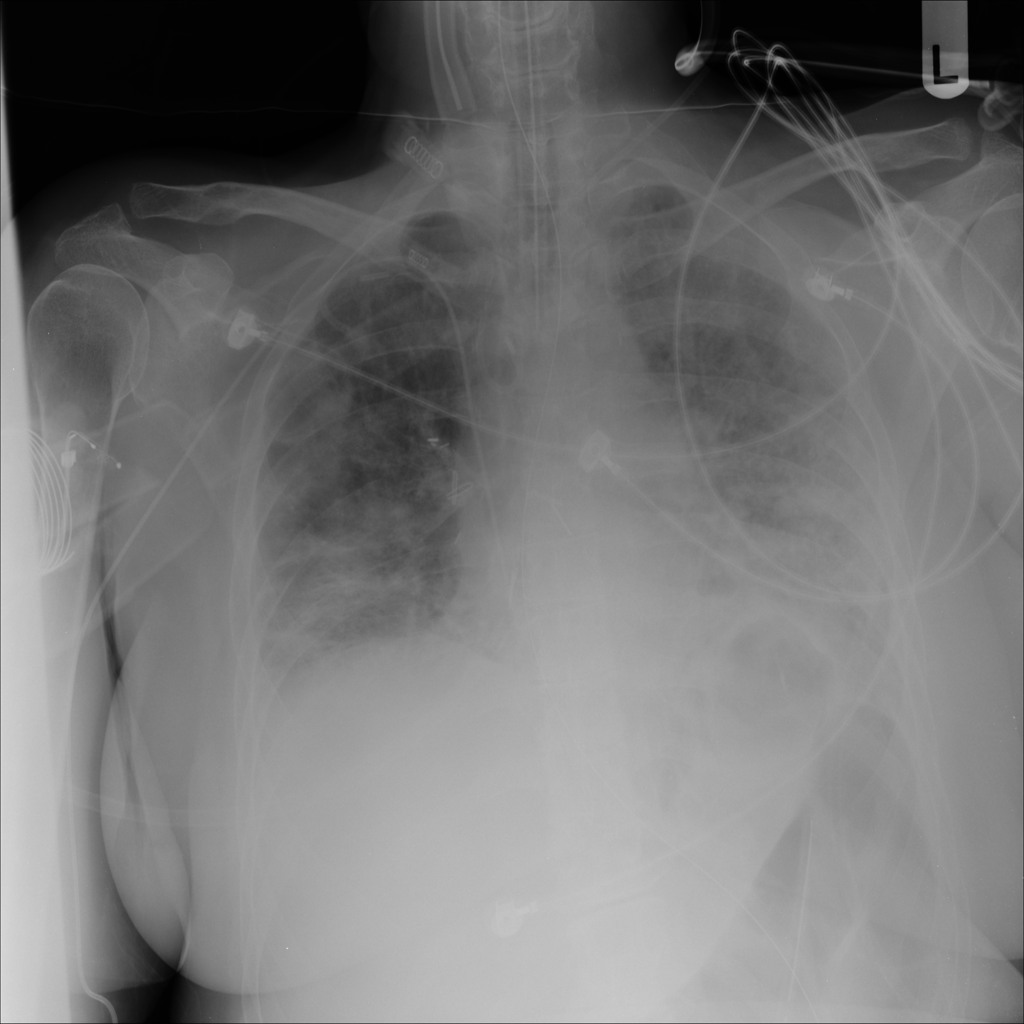

PAT-3384 · IMG-054Atelectasis

PAT-3384 · IMG-054

AP